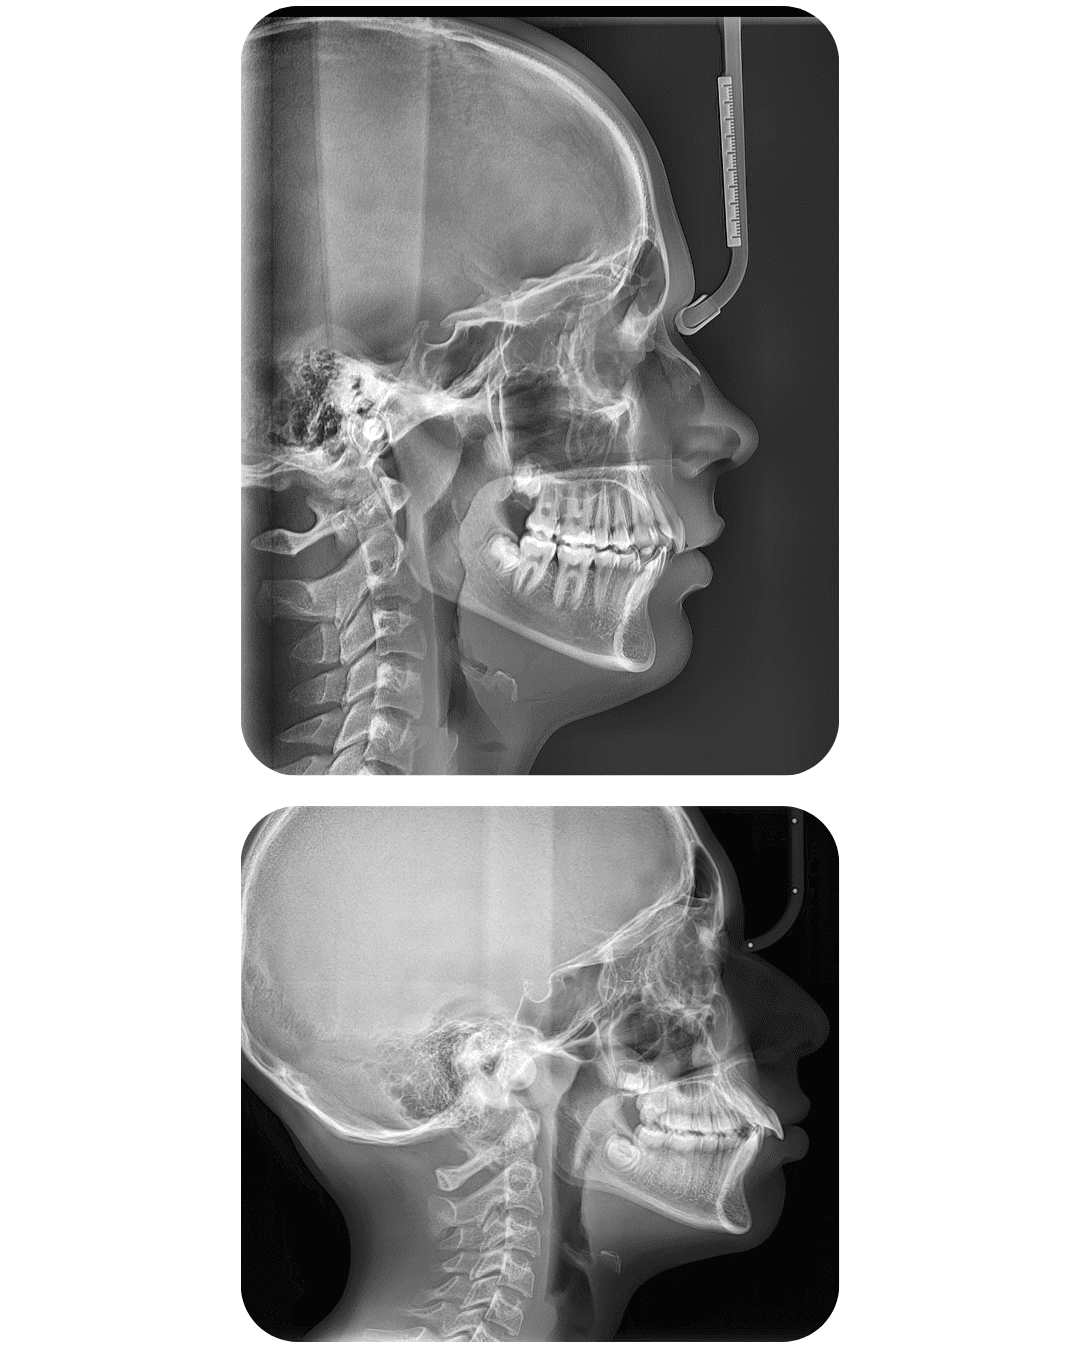

TELERENTGEN

Telerentgen nudi detaljnu ortodontsku dijagnostiku, omogućujući detaljan uvid u rast čeljusti i profil lica te planiranje terapije s maksimalnom točnošću.